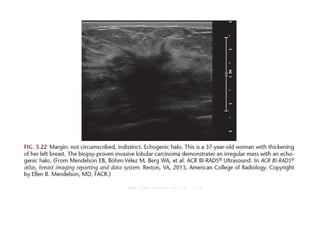

The margin of a lesion can be:

Circumscribed (historically well-defined This is a benign finding.

Obscured or partially obscured, when the margin is hidden by superimposed

fibroglandular tissue. Ultrasound can be helpful to define the margin better.

Microlobulated. This implies a suspicious finding.

Indistinct (historically ill-defined).

This is also a suspicious finding.

Spiculated with radiating lines from the mass is a very suspicious finding.